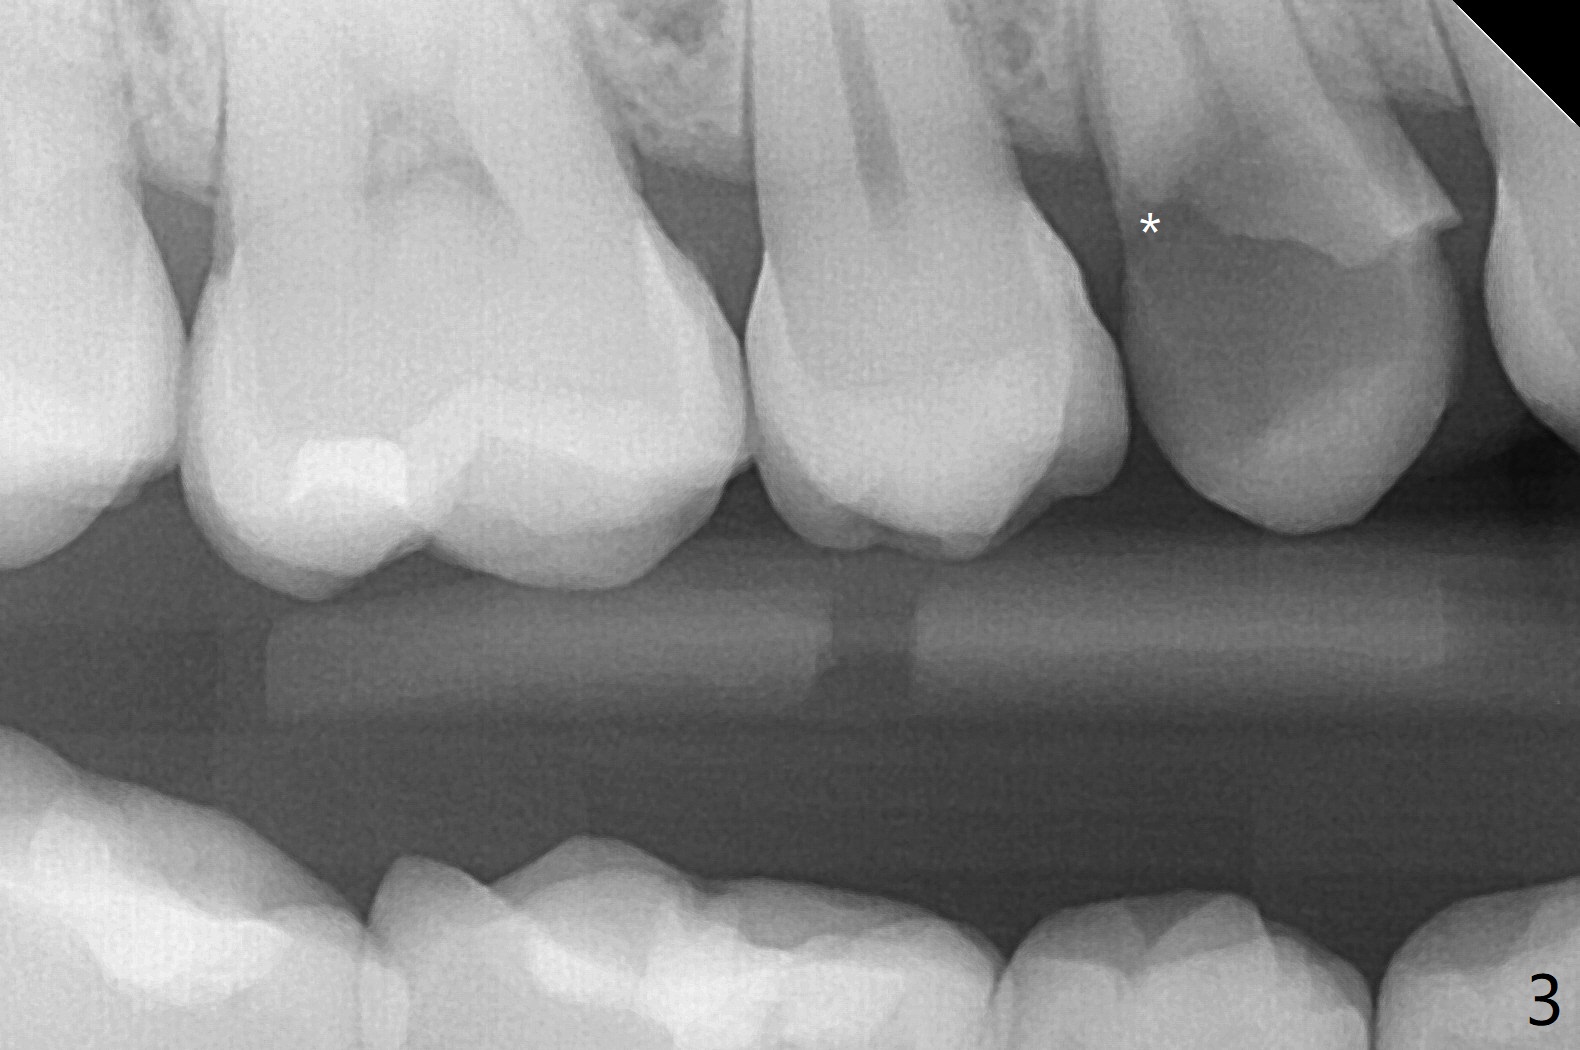

今天临床实践让我对植骨概念和操作有两方面突破,与大家分享讨论。PRF/sticky bone(粘性骨粉)以及血小板因子(成品)对软硬组织缺损修复重建无疑起到不可缺少作用。但是大多数拔牙病例并不是那么严重,放置骨粉和覆盖胶原膜足够了。为了避免费时的缝线固定胶原膜,介绍一种简易固定方法,助手可以做。31岁女不想保留严重龋坏右上4(图一至四,拍摄临床照片,与后期比较,但愿简易植骨不产生骨板塌陷),虽然术前根尖片显示根尖阴影(图四),术中没有根尖骨板缺失。估计没有严重骨板缺损,她又年轻,再生能力强,所以做简易植骨(异体骨,图五),也就是不需要PRF或者血小板因子,骨粉表面放置GEM CAP(9-12月吸收膜),由胶水固定(图六),在放置牙周敷料前,在胶原膜表面涂一层含有抗单纯疱疹病毒凡士林(图七),但愿敷料脱落时,不至于把胶原膜带下来。术后第六天,病人由于左上第二磨牙不适回来,说敷料脱落,没有不适,要求检查,其实膜也丢失(图八,九),骨粉好像挺稳定,没有做如何处理,尽管少量骨粉离开牙槽窝(<)。